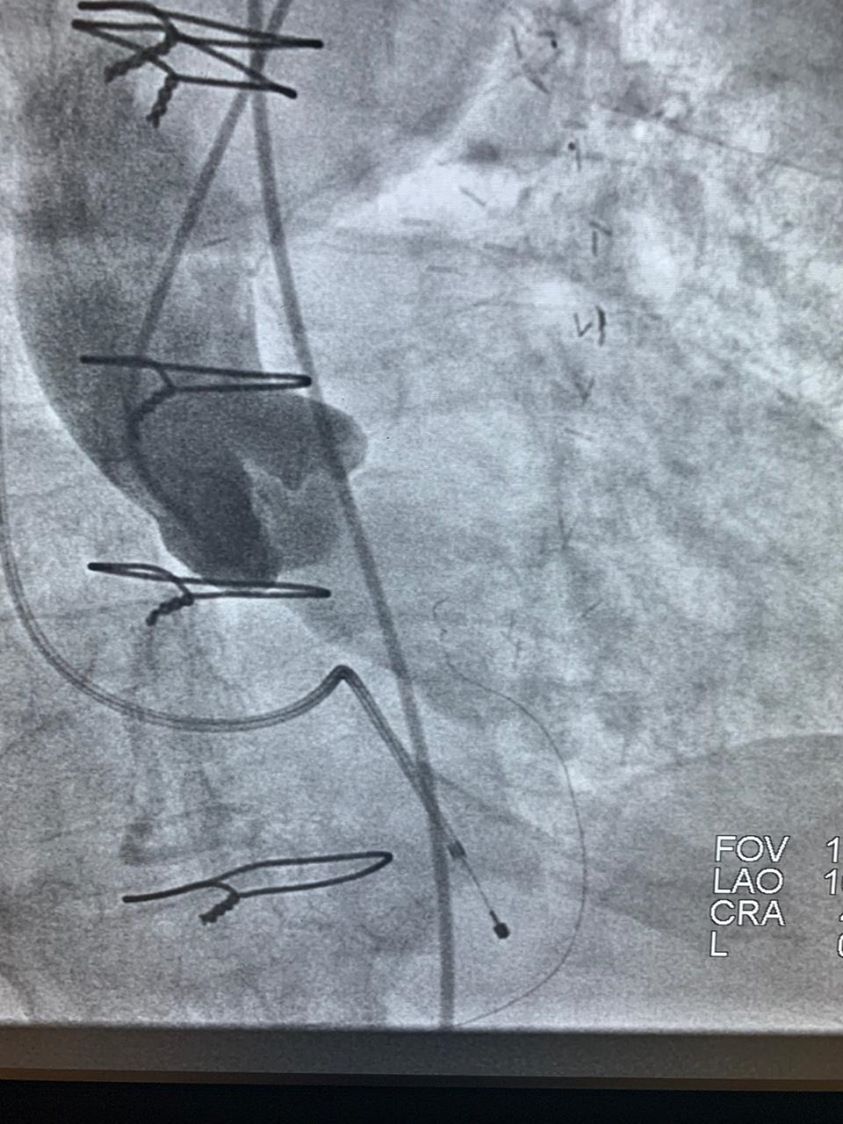

TAVI & TAVR